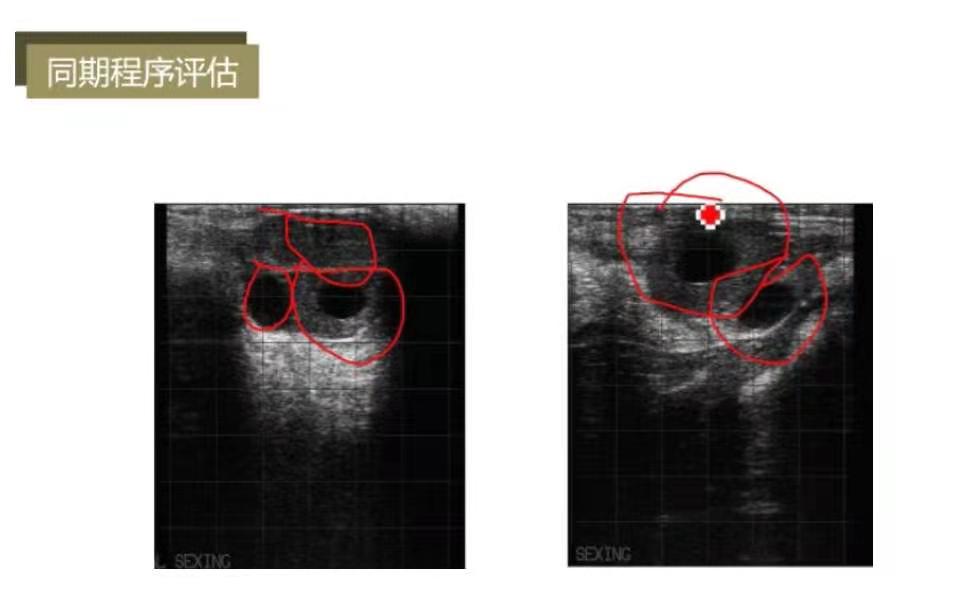

同期程序0789方案的评估节点为第7天打PG时的卵巢状态,即有双黄体是***佳状态。左图为实心黄体+空腔黄体+优势卵泡,说明同期程序执行较好;右图为空腔黄体+优势卵泡,预同步的几针无效或复旧较晚。